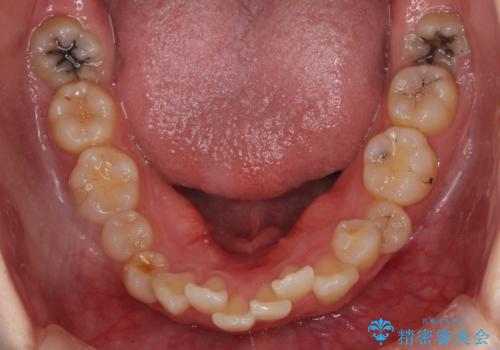

下顎の大臼歯が前に倒れこんでいたため、矯正用ミニスクリューで後ろに起こしています。

治療の難易度としてはかなり高めでしたが、無事終了することができました。